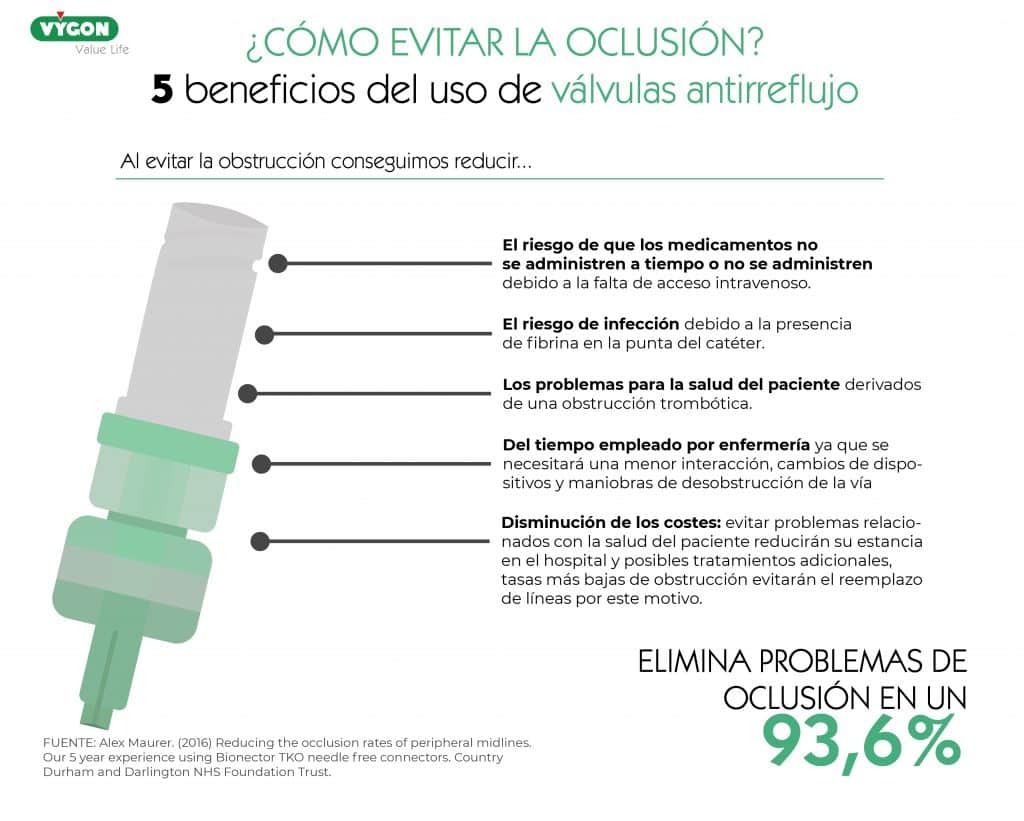

- Válvulas antirreflujo: Se trata de una válvula de control del fluido bidireccional, la cual permanece cerrada hasta que la fuerza de infusión o extracción alcanza una presión especifica y, a medida que la presión de infusión o extracción empieza a reducirse, la válvula vuelve a cerrarse. Consiguen eliminar problemas de obstrucción hasta en un 93,6% de los casos.

Las válvulas antirreflujo consiguen eliminar problemas de obstrucción en un 93,6% de los casos.10

Como hemos comentado, contar con válvulas antirreflujo nos permitirá eliminar problemas de obstrucción en un 93,6% de los casos.10 De esta forma, evitando la oclusión conseguiremos:

- Reducción del riesgo de que los medicamentos no se administren a tiempo o no se administren debido a la falta de acceso intravenoso. 10

- Menor riesgo de infección debido a la presencia de fibrina en la punta del catéter. 2,4

- Reducción de los problemas para la salud del paciente derivados de una obstrucción trombótica. 10

- Reducción del tiempo empleado por enfermería: necesidad de menor interacción, cambios de dispositivos y maniobras de desobstrucción de la vía. 10

- Disminución de los costes: el reemplazo de líneas debido a la obstrucción, retraso en el tratamiento con las posibles consecuencias y tratamientos adicionales que esto puede suponer, estancias más prolongadas por problemas derivados de la obstrucción, equipo/enjuagues de heparina adicionales y el mayor tiempo de enfermería tienen una gran repercursión en el coste de la estancia del paciente. 10